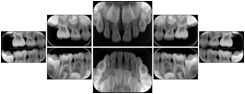

2. A patient requests cosmetic surgery to enhance their facial appearance. The case requires consultation between an orthodontist in New York and an oral surgeon in California. The cephalometric series of 2D projections constructed from a volumetric CT data set that is used for the discussion is arranged by a Structured Display for transfer between the two practitioners.

Cephalometric Series Structured Display

Figure OO-2. Cephalometric Series Structured Display